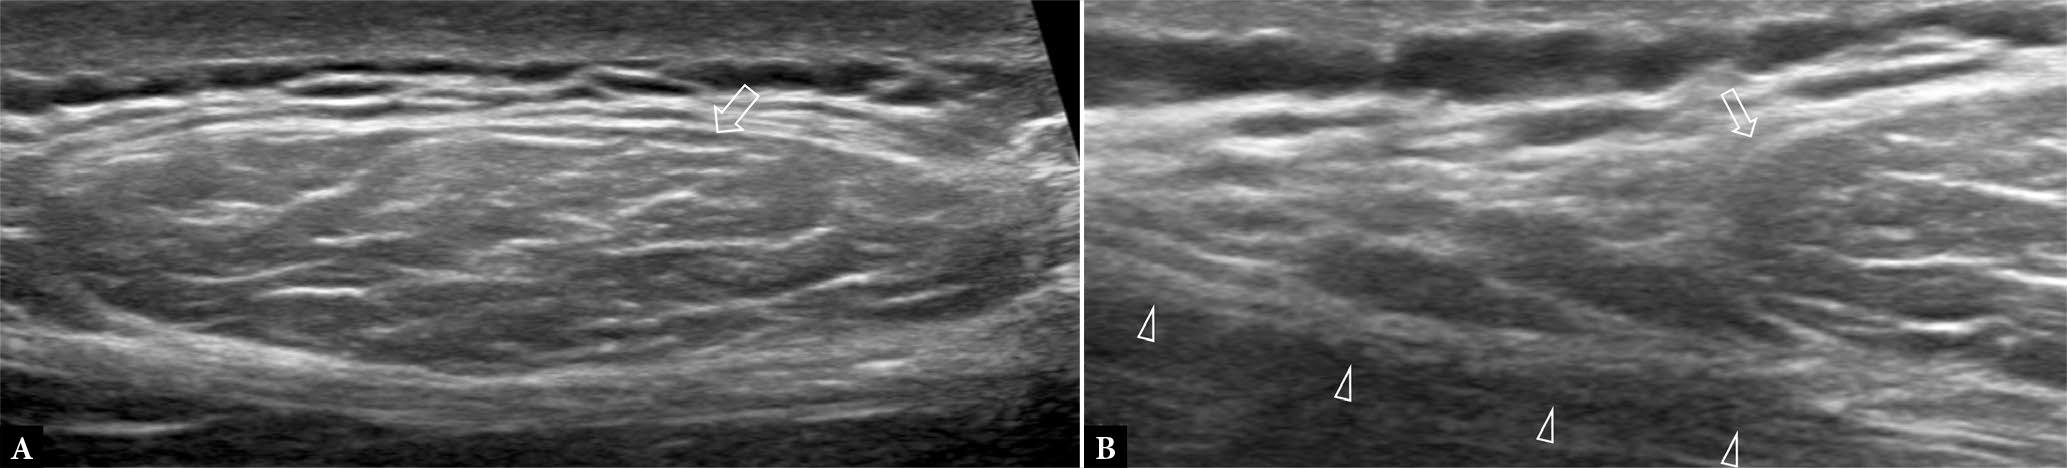

Fig. 6.

62-year-old female with slow-growing radial-sided wrist mass for two years. A. Longitudinal, B. transverse greyscale and C. longitudinal color Doppler US show a soft tissue mass (arrowheads) surrounding the 1st extensor compartment tendons (*), compatible with giant cell tumor of tendon sheath (GCTTS). Dynamic ultrasound can help to exclude intratendinous extension. GCTTS was confirmed on surgical excision